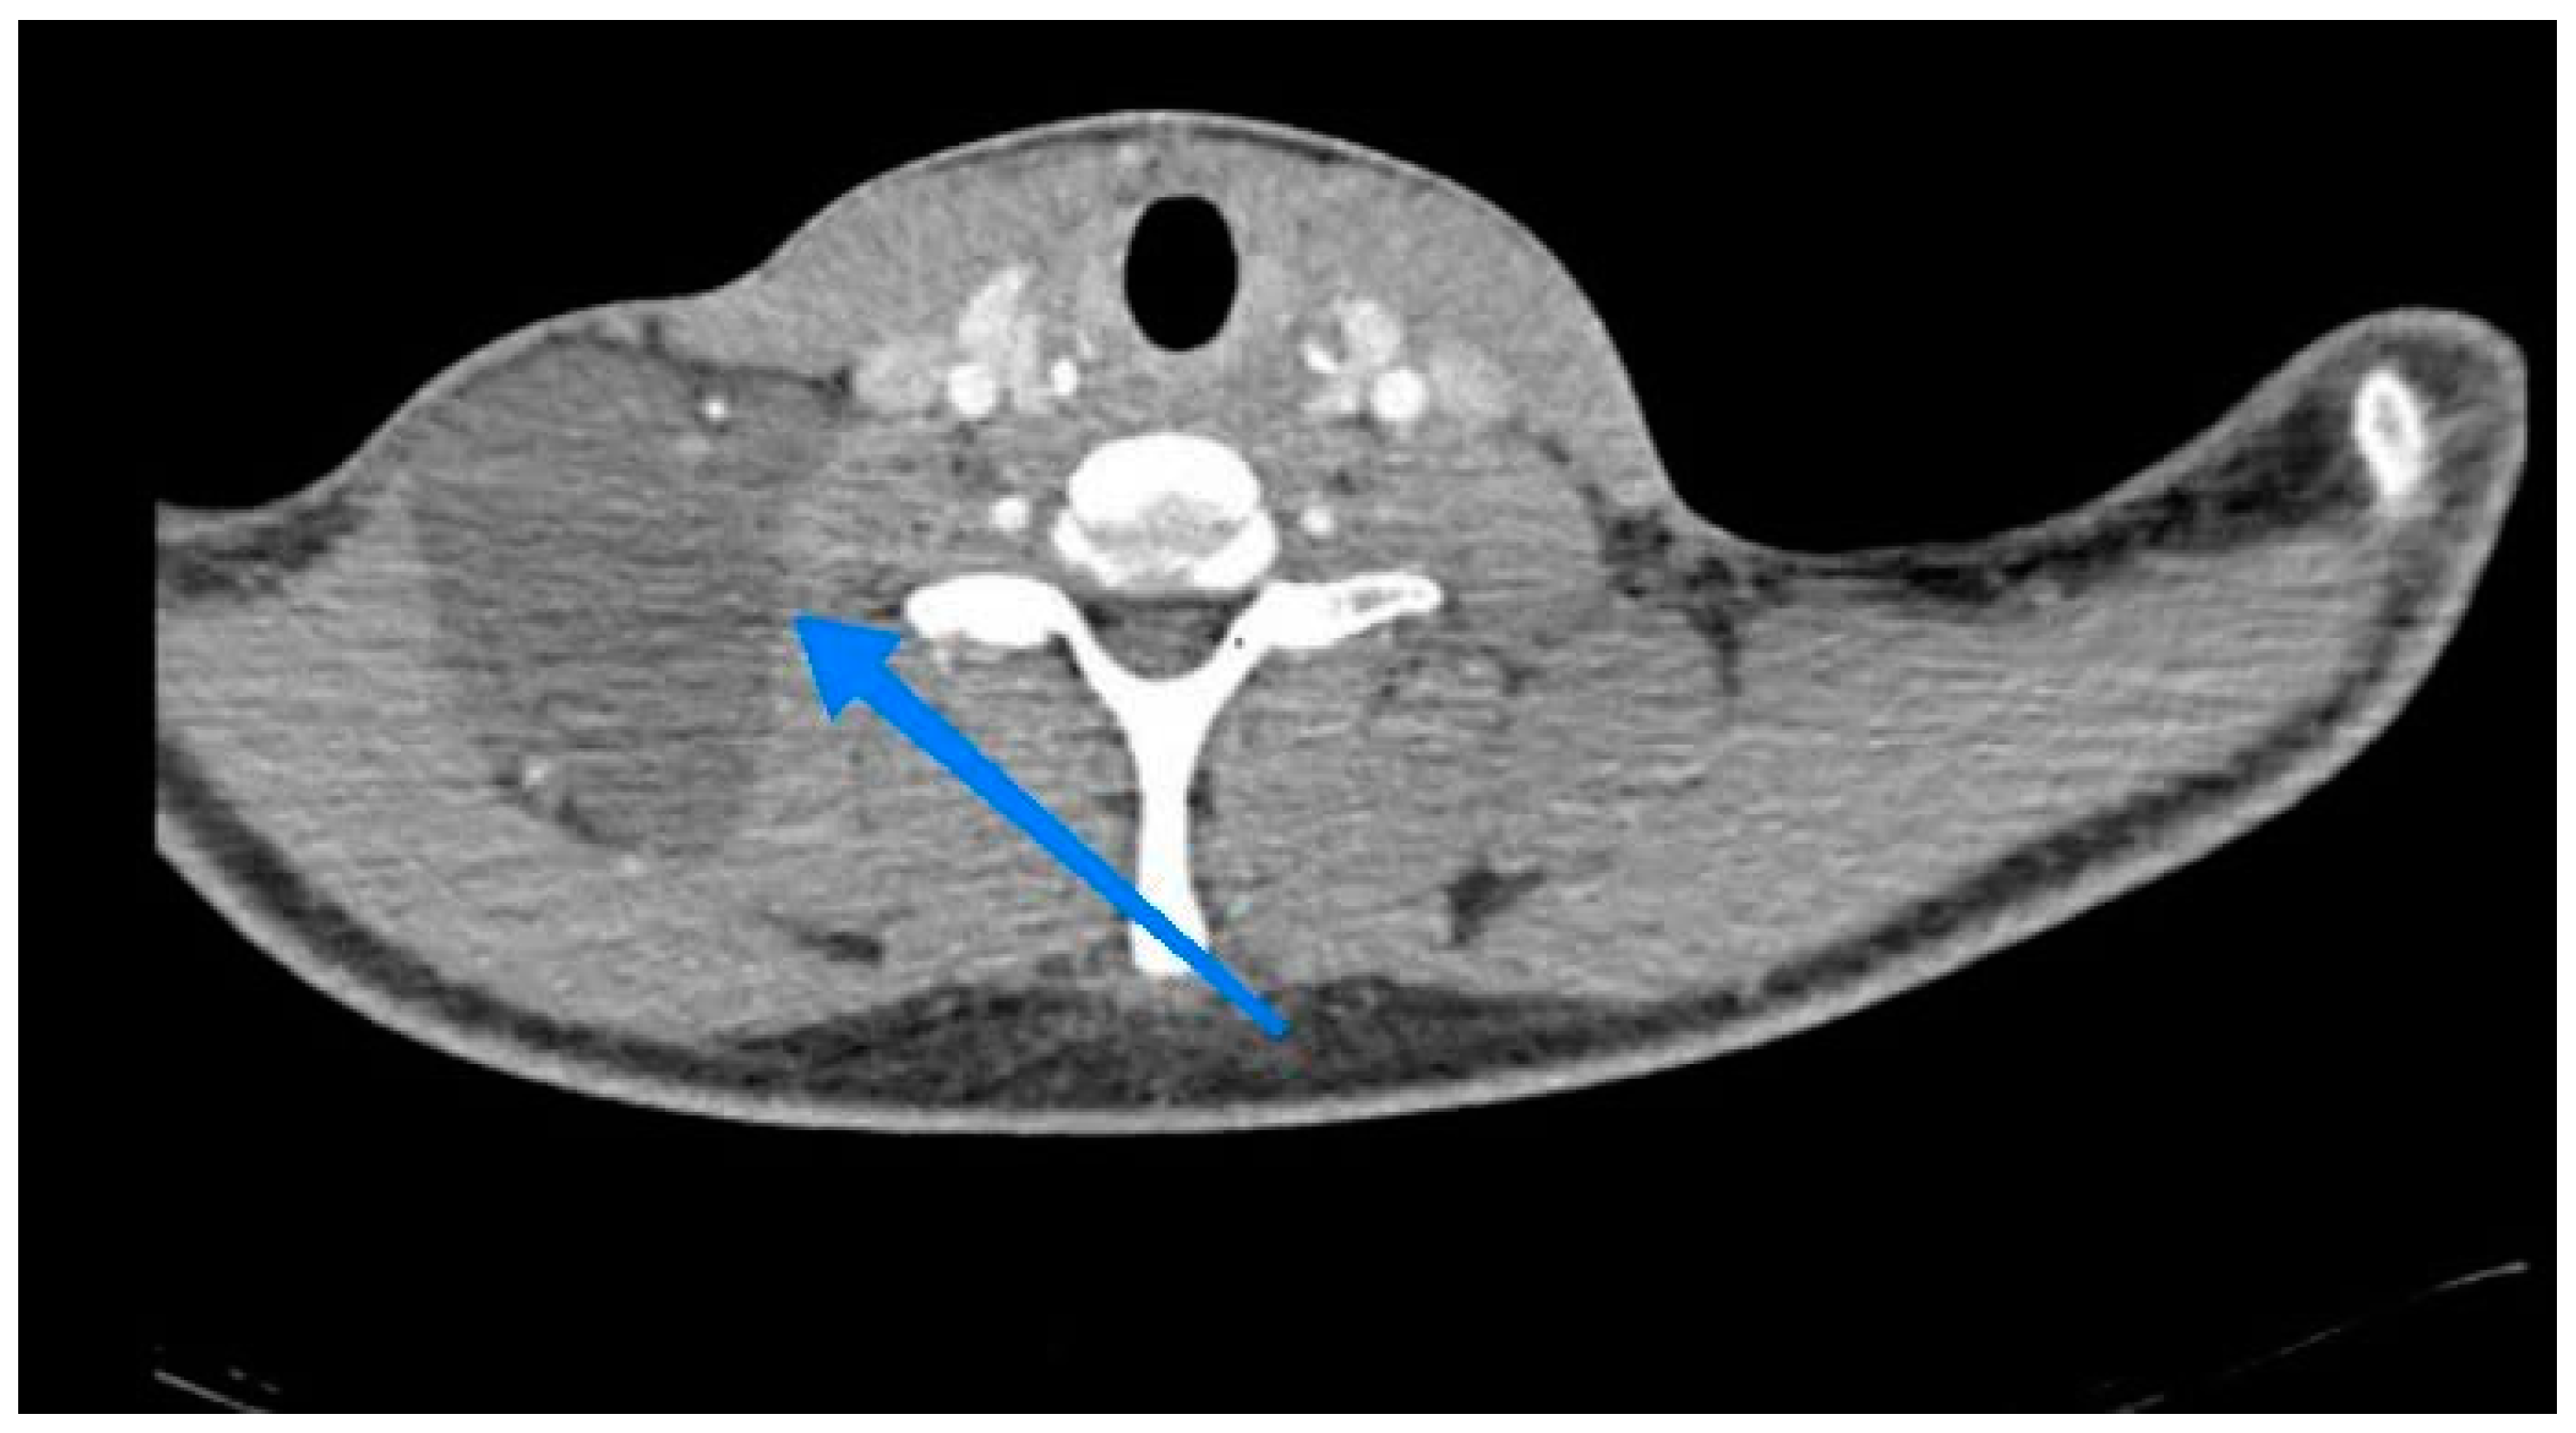

The spiral chest CT scan with and without contrast was normal but in the spiral with and without contrast Neck CT Scan was a multi-lobulated hypodense area at supraclavicular regions measuring about 82*42 mm Suggestive of cystic hygroma. This is shown in Figure 2.

Figure 2. Sagittal and Coronal view of the Neck CT Scan.